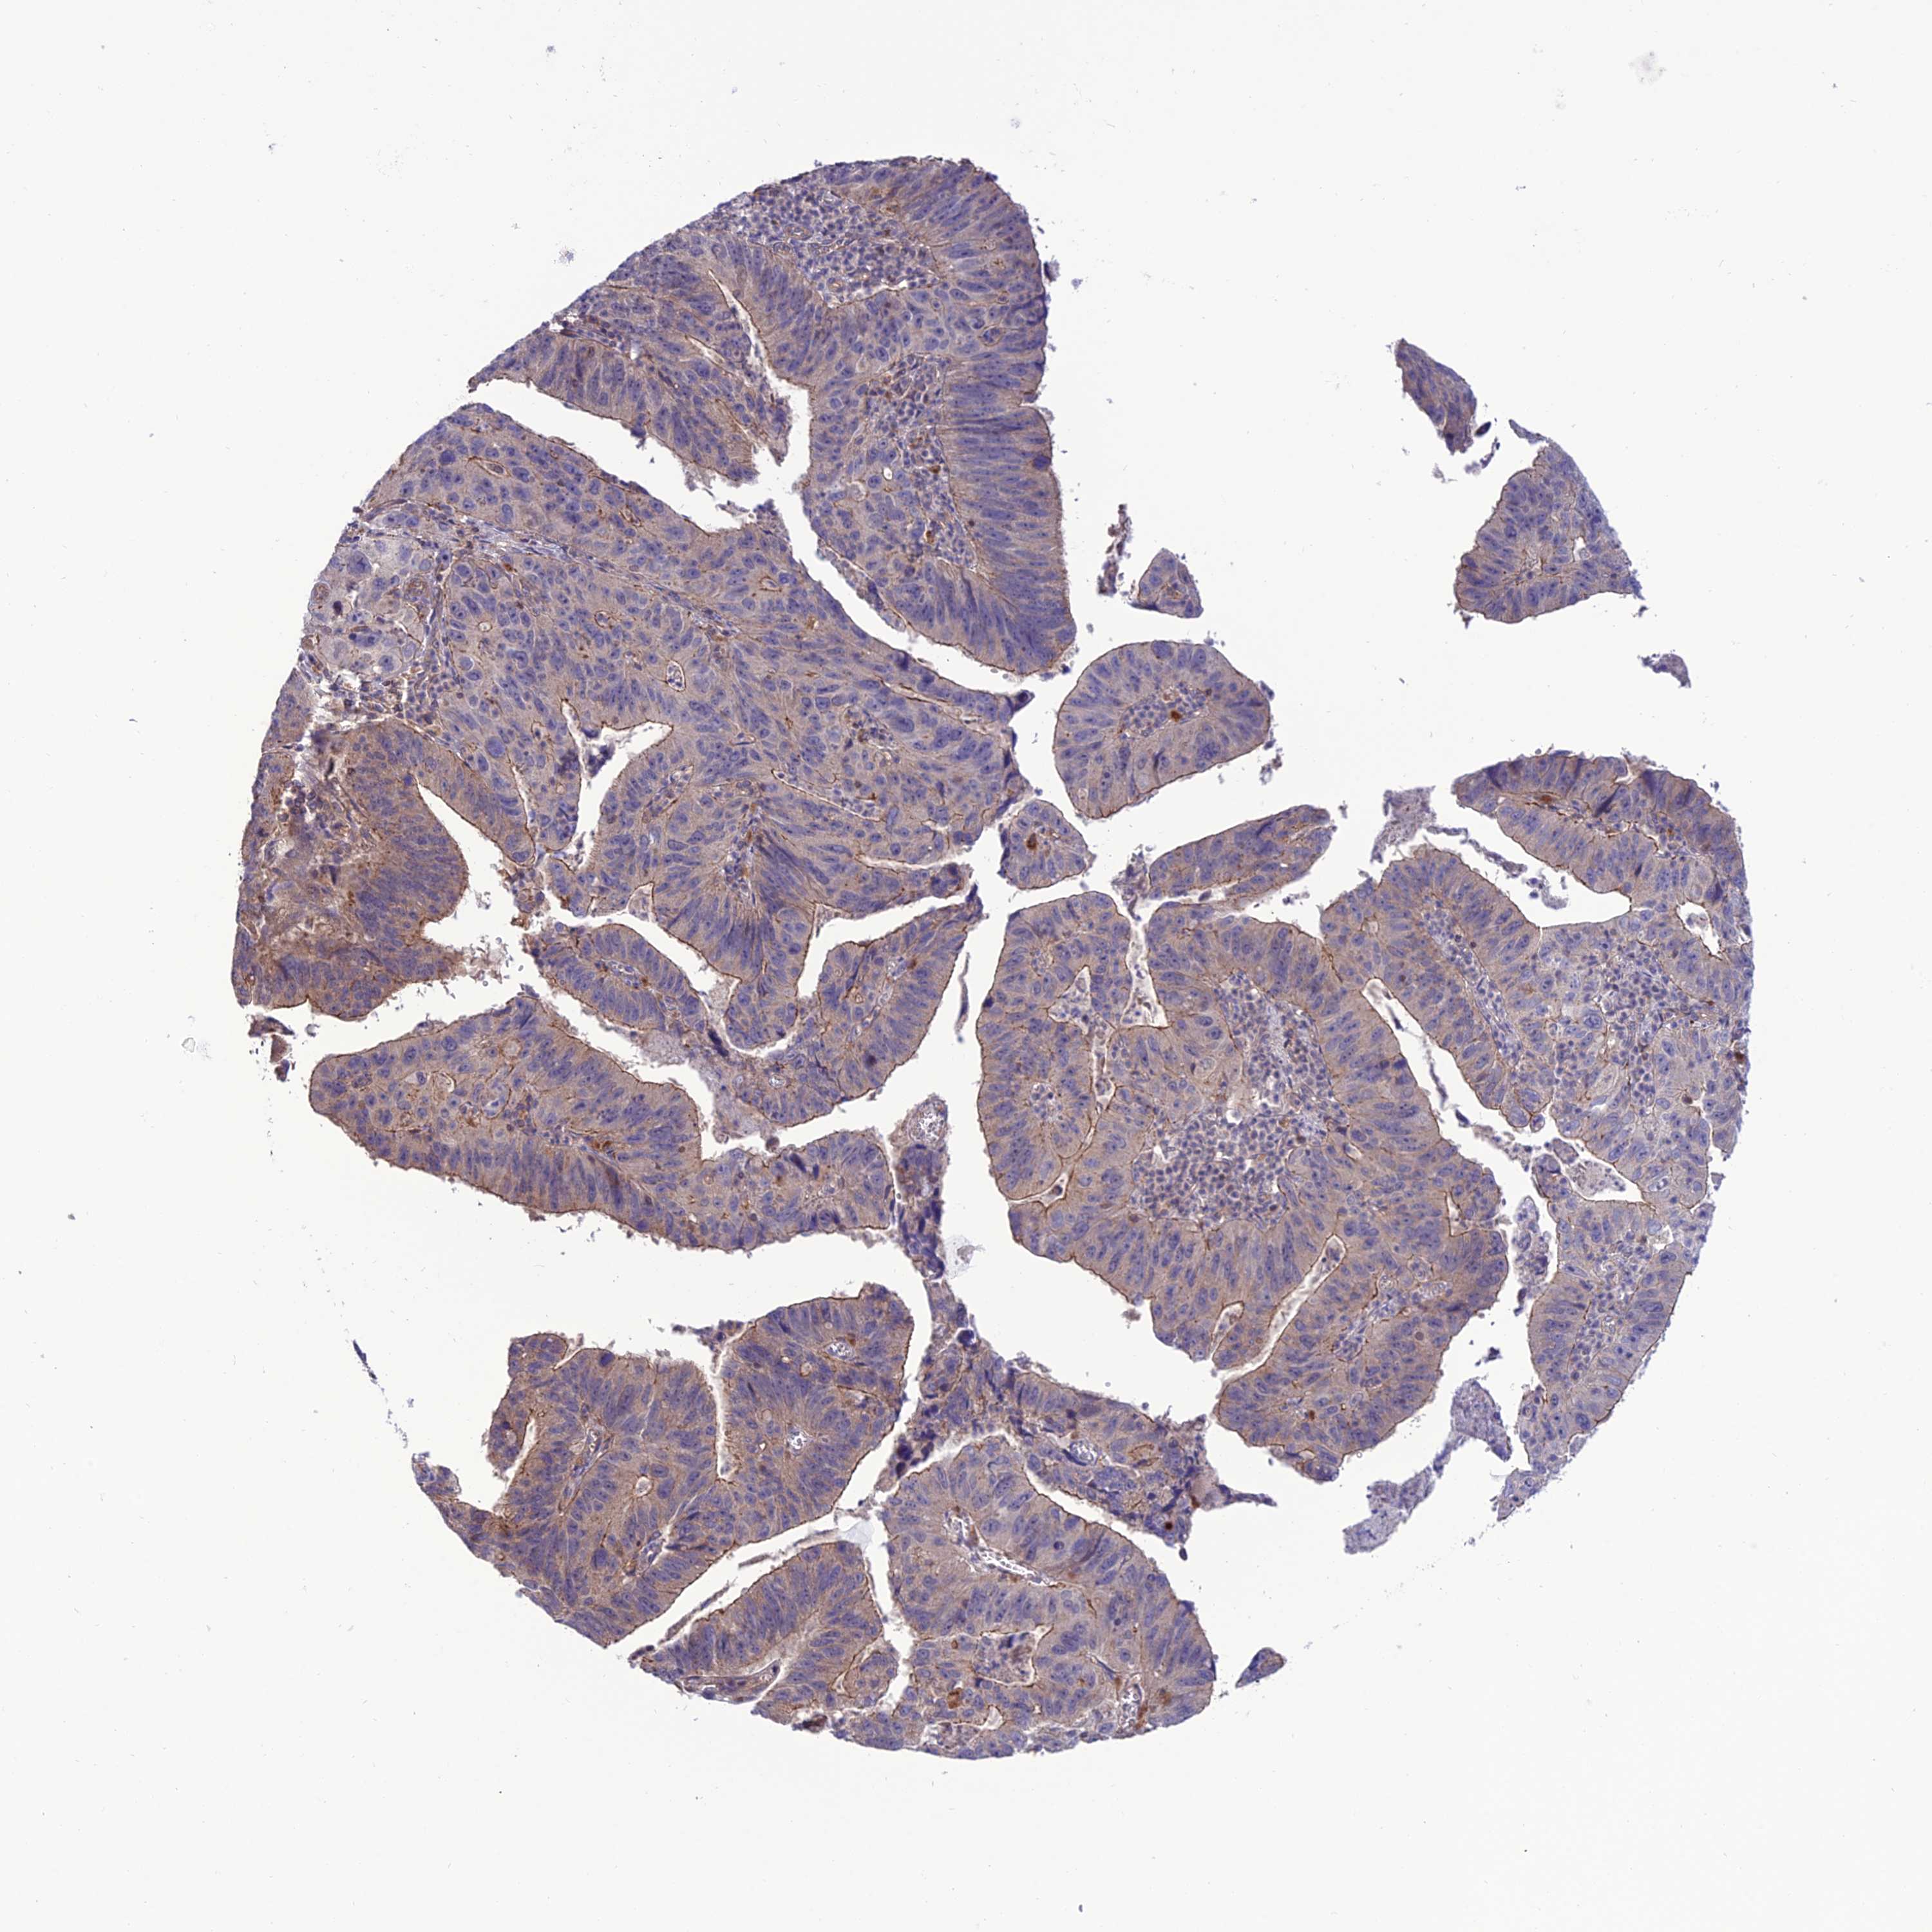

STOMACH CANCER - Protein expressioni

A mouse-over function shows sample information and annotation data. Click on an image to view it in a full screen mode. Samples can be filtered based on level of antibody staining by selecting one or several of the following categories: high, medium, low and not detected. The assay and annotation is described here.

Antibody stainingi

Antibody staining in the annotated cell types in the current human tissue is reported as not detected, low, medium, or high, based on conventional immunohistochemistry profiling in selected tissues. This score is based on the combination of the staining intensity and fraction of stained cells.

Each image is clickable and will lead to virtual microscopy that enables deeper exploration of all samples and also displays staining intensity scores, fraction scores and subcellular localization as well as patient and tissue information for each sample.

Antibody HPA040765

Staining

High

Medium

Low

Not detected

Intensity

Strong

Moderate

Weak

Negative

Quantity

>75%

75%-25%

<25%

None

Location

Nuclear

Cytoplasmic/membranous

Cytoplasmic/membranous,nuclear

Adenocarcinoma, NOS